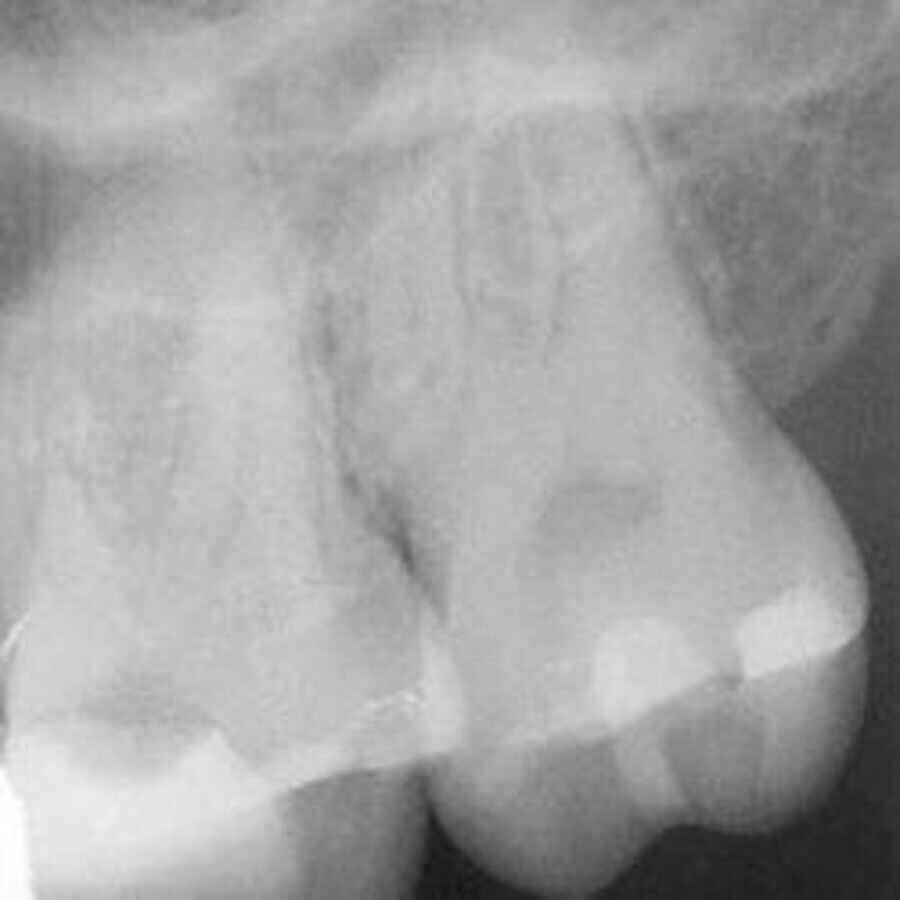

笔者选择进行单次的牙髓治疗。首先进行局部麻醉给药和橡皮障隔离。之后使用金刚砂车针开髓,并用超声工作尖(CAVI 2-D,VDW)找到根管口。开髓过程中使用探针探查到4个根管。腭根管的工作长度为21.5mm(C-PILOT,ISO 10号,VDW),近颊根管和远颊根管的工作长度为21.0mm(C-PILOT,ISO 10号),近颊第二根管的工作长度为20.0 mm(C-PILOT,ISO 8号)。使用电子根尖定位仪对工作长度进行确认。从全景片和牙片(图2)上可以发现,根管十分狭窄、弯曲,因此笔者决定使用连续旋转根管预备系统(VDW.ROTATE,VDW)。

图2:初始X线片。